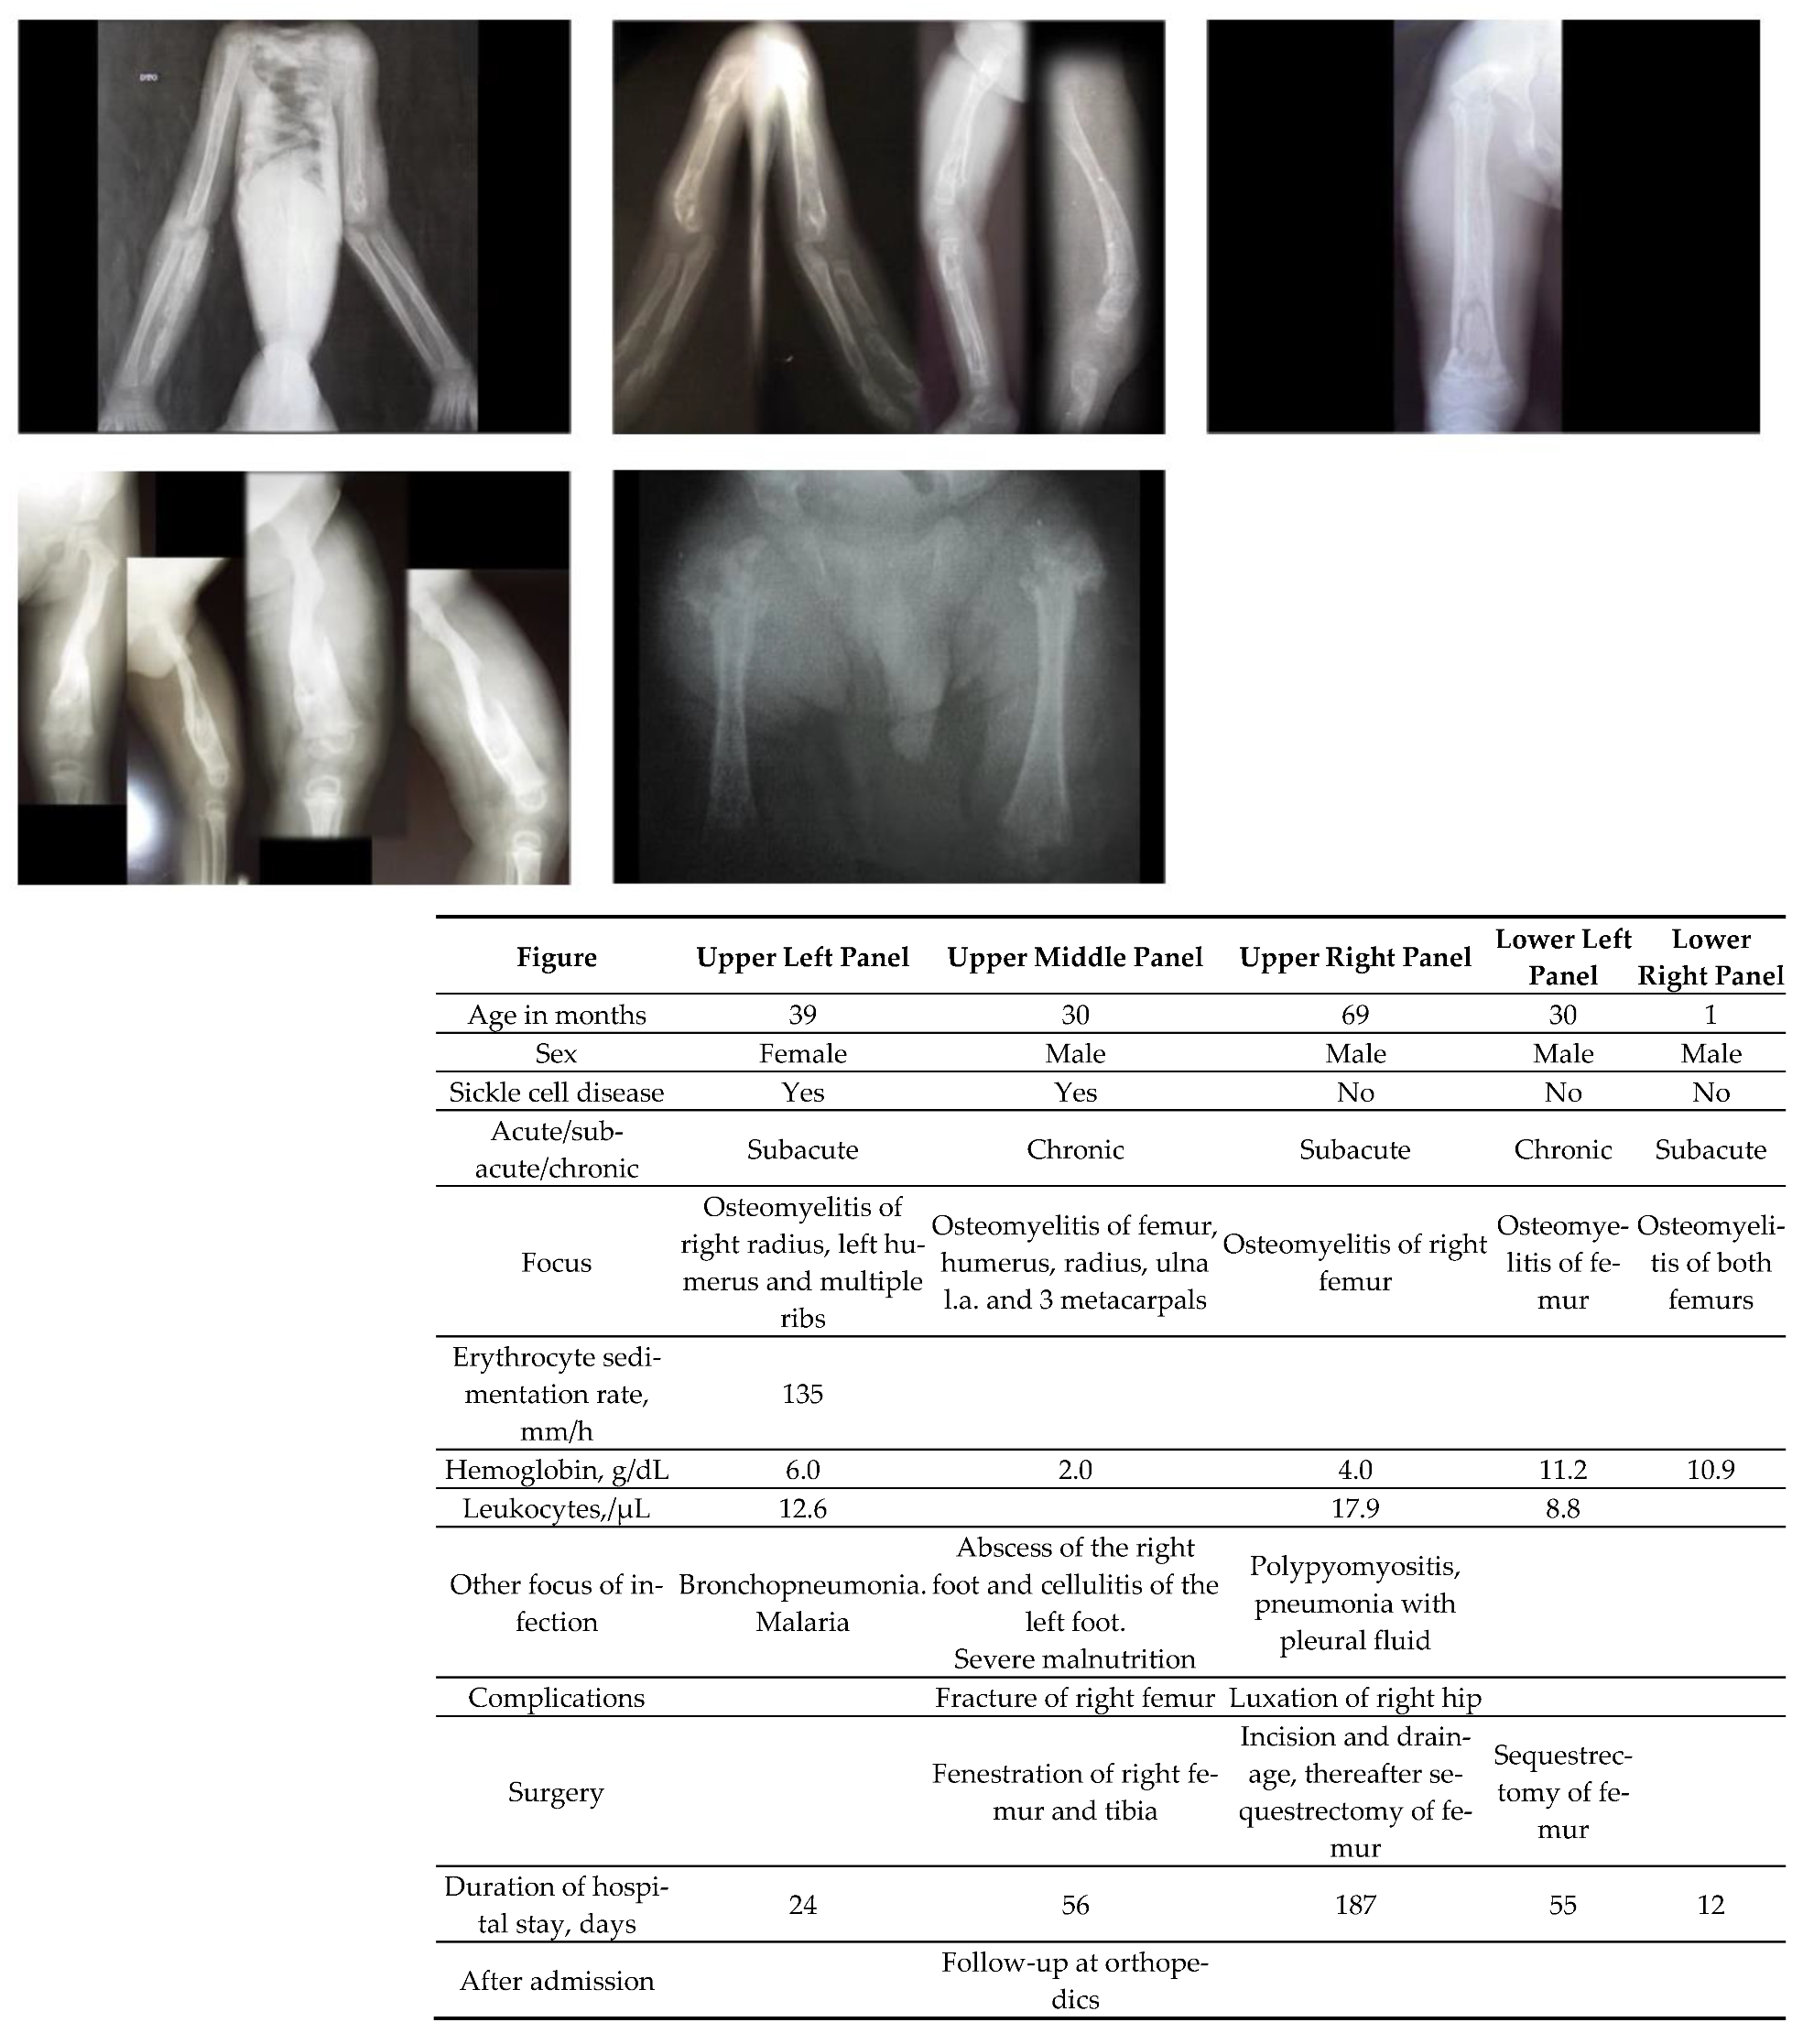

A total of 71% (30/42) of patients were febrile and in 54% (20/37) of patients the fever lasted longer than one week. Blood transfusion and supplemental oxygen were given to 38% (17/45) and to 18% (8/45) of patients. A pathologic fracture developed in 31% (14/45) of the patients, of whom 64% (29/45) underwent surgery, traction being used in 4 cases (9%). Median (IQR) duration of antibiotics was 28 days (40). Antimalarials were given to 6 children (13%). Median length of stay in hospital was 31 days (IQR 47). Figure 1 shows severe osteomyelitis in 5 children.

Empirical antibiotic treatment is commonly given to children with SCD suffering from bone pain of unknown cause [15]. Understanding the pattern of symptoms in osteomyelitis may help to better target the treatment. The clinical features and findings used to differentiate osteomyelitis from a vaso-occlusive crisis in SCD patients are fever (> 38.0°C) and pain in a single area in the diaphysis of a long bone [16]. In our series, fever was present in 8–9 out of 10 patients. Multiple bone involvement was however not that uncommon a finding, as seen in Figure 1.

Figure 1. Severe osteomyelitis in 5 children. Patient characteristics are given above.